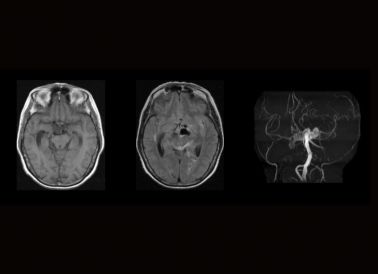

ÔÀíÏÈÈÝ:3D-TOF-MRAÊÇÒ»ÖÖÎÞ´´ÐÔµÄѪ¹Ü¼ì²éÊÖÒÕ£¬Ê¹Óà MRI ³ÉÏñÊÖÒÕÀ´Ãè»æÆÊ½â×éÖ¯ÖÐѪ¹Ü·¾¶²¢Èýάչʾ³öÀ´µÄÒªÁ죬¶Ô¶¯ÂöÌØÊâÃô¸Ð£¬ÎÞÐè×¢Èë±ÈÕÕ¼Á£¬ ¿ÉʹѪ¹ÜÏÔÓ°

ÁÙ´²ÓÃ;:MRAÄÜÖ±½ÓÏÔʾ¶¯ÂöÁö¾Þϸ¡¢²¿Î»¡¢ÐÎ×´£¬Äܶ෽λ¶à½Ç¶ÈÊÓ²ìÁöÌåÕûÌåÇéÐΣ¬3D-TOF-MRA°ÐѪ¹ÜÖØ×éµÄÒªÁìÕë¶ÔÖØµã²¿Î»¾ÙÐÐÆÊÎö£¬Ìá¸ß¶¯ÂöÁö&С¶¯ÂöÁöÕï¶ÏµÄ׼ȷÐÔ